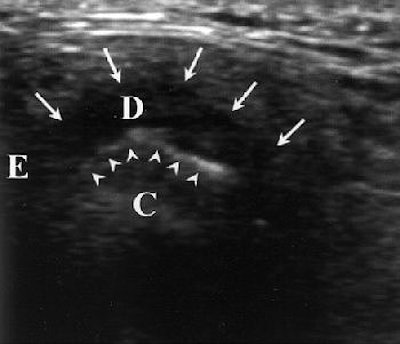

| Temporomandibular joint (TMJ) of 32-year-old woman. Diagnosis of disk displacement with reduction was based on MR imaging findings. Longitudinal high-resolution sonogram obtained in closed-mouth position shows anterosuperior TMJ compartment and disk (arrows) anterior to condyle (arrowheads). E = articular eminence, D = disk, C = condyle. Emshoff R, Jank S, Bertram S, Rudisch A, Bodner G, "Disk Displacement of the Temporomandibular Joint: Sonography Versus MRI," (AJR 2002; 178: 1557-1562). |